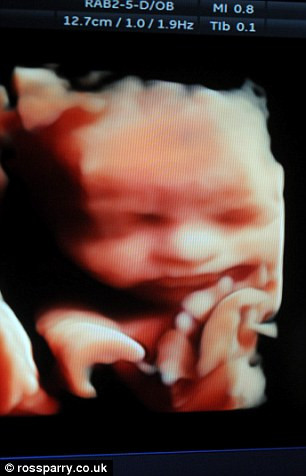

(Kiến Thức) - Giờ đây, mẹ bầu sẽ không cần mường tượng thiên thần nhỏ trong bụng như thế nào. Họ có thể sờ nắn, ngắm nghía một hài nhi 3D thực sự.

Mọi người đều thích trẻ sơ sinh nhưng ôm ấp bé trước khi được sinh ra thực sự quá khó. Lúc này, bạn có thể ôm ấp một bào thai 3D của chính bạn từ một máy quét siêu âm.

Một doanh nghiệp ở Tarleton, Lancashire, Tây Bắc nước Anh hiện đang cung cấp dịch vụ sáng tạo in hình 3D thai nhi. Cha mẹ có thể đóng khung và treo nó ở nhà.

Nếu cha mẹ muốn có hình 3D em bé thì sẽ cung cấp dữ liệu siêu âm cho công ty và sau đó, dữ liệu này sẽ được chuyển đổi thành định dạng 360 độ đặc biệt trước khi chuyển thành mô hình 3D.

Sản phẩm cuối cùng có chiều dài hơn 20cm, trông giống như một chiếc mặt nạ.

Các mẹ bầu có thể lựa chọn hình ảnh thai nhi từ tuần thứ 28 trở đi để làm mô hình, khi em bé đã phát triển đầy đủ.

Mô hình bào thai 3D này có giá khá đắt, gần 5 triệu đồng.